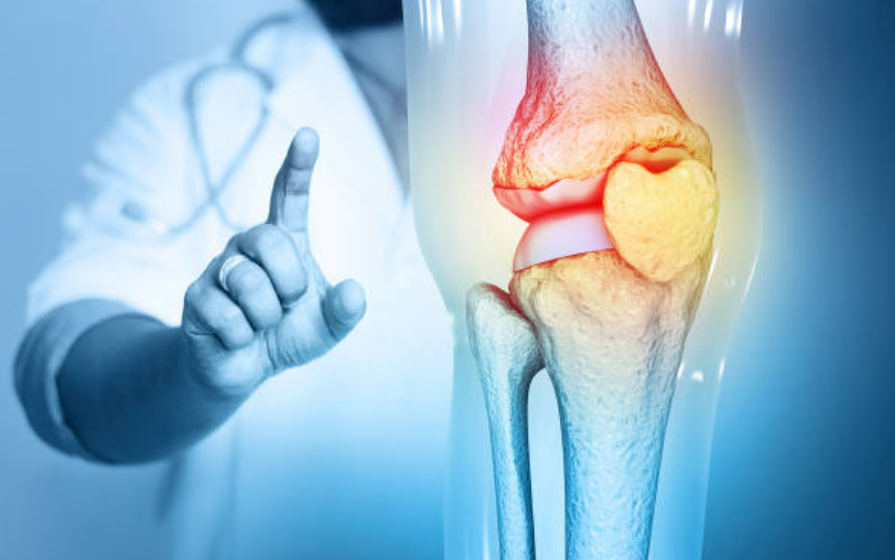

관절염은 관절에 염증이 생기는 만성적인 질환입니다. 주로 류마티스 관절염과 퇴행성 관절염으로 나뉘며, 이들은 다른 원인과 증상을 가지고 있습니다. 관절염은 주로 연령에 따라 발생하는데, 중년 이후에 더 흔하게 발생합니다. 이러한 질환은 관절의 기능을 제한하고 일상생활에 불편을 초래할 수 있습니다.

류마티스 관절염은 자체 면역 시스템이 관절을 공격함으로써 발생합니다. 면역 시스템의 과도한 반응은 관절염의 주요 원인으로 작용하며, 이로 인해 관절의 염증과 통증이 발생합니다. 퇴행성 관절염은 연령과 노화에 따라 발생하는데, 연령에 비례하여 연골의 퇴화가 진행됩니다. 이러한 연골의 퇴화는 관절의 마찰, 염증 및 통증을 초래합니다.